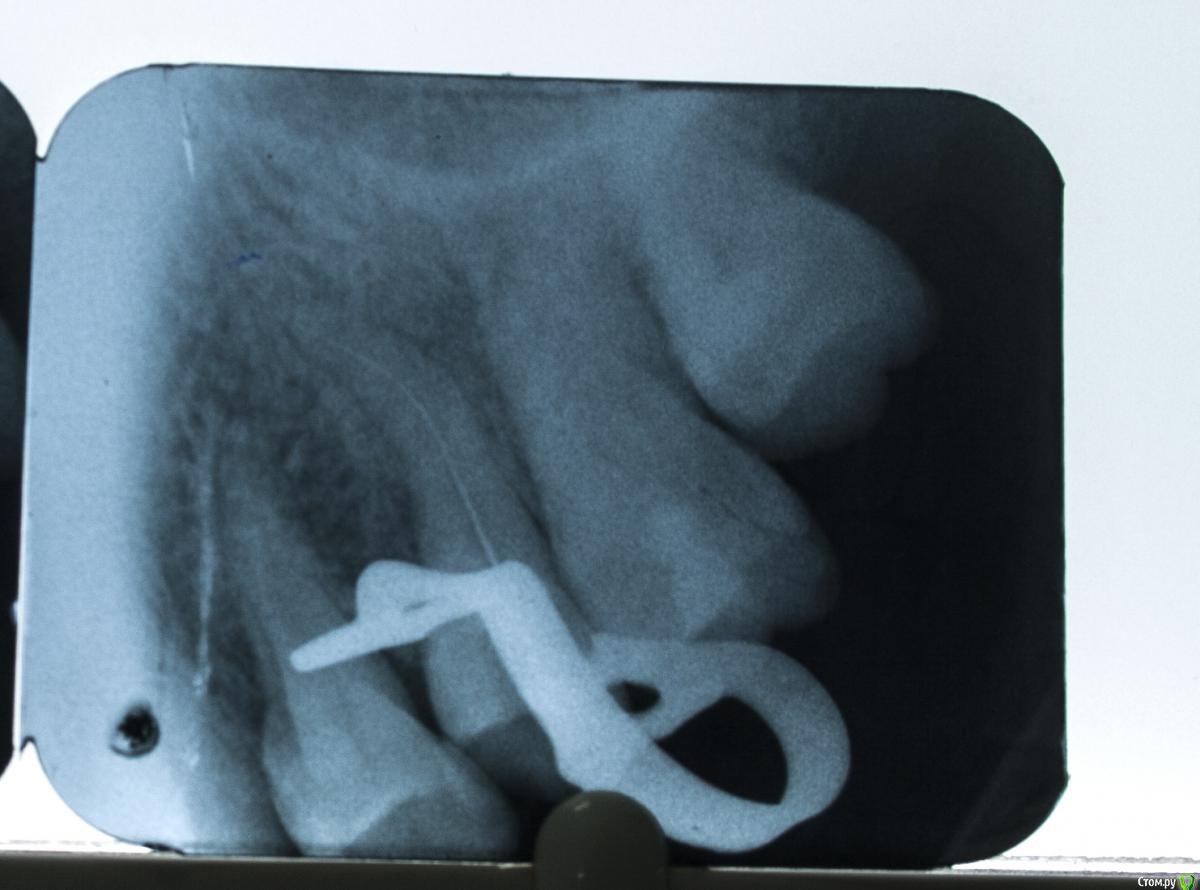

St. Опубликовано 14 июня, 2015 Автор Поделиться Опубликовано 14 июня, 2015 Собственно сегодня боль у пациентки локализовалась, показывала четко на 15. Р-ия на холод ноющая, перкуссия чувствительна. Решили депульпировать. Открыла, получила сукровично-гнойный экссудат в достаточно большом количестве. Отмыла, экссудата много, оставила гидроокись. Кто что думает о причине поражения 15?Вот снимок в процессе работы Ссылка на комментарий